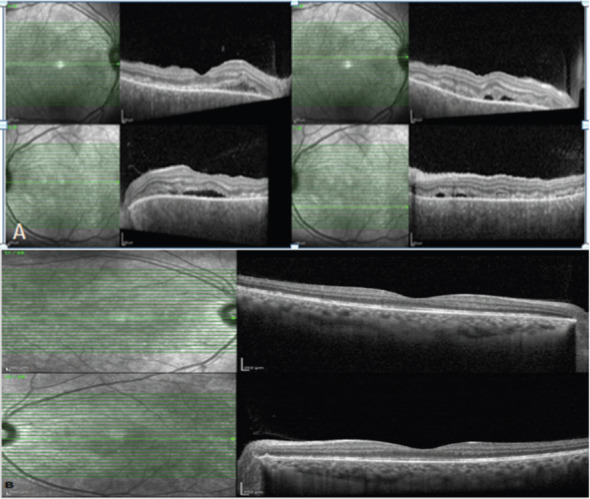

Case: We describe a case of a 32-year-old healthy lady who was admitted to neurology with the initial impression of aseptic meningitis. She had subacute onset of headache and fever, associated with blurring of vision and painful eye movements. Visual acuity 20/250 of the right eye and 20/80 of the left eye. Intra-ocular pressure measured 12 for the right eye and 14 for the left eye, and extraocular muscle movements were full Slit lamp examination showed a quite conjunctiva and clear cornea; however, there was an anterior chamber reaction of 2+ cells. The fundus exam showed mild vitritis with hyperemic disc swelling of both eyes and exudative retinal detachment bilaterally. Macular optical coherence tomography (OCT) demonstrated the presence of vitritis, pockets of subretinal fluids with bacillary layer detachment, and choroidal thickening. She was treated with steroids and mycophenolate mofetil with an excellent outcome.